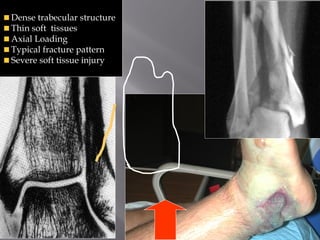

Dense trabecular structure

Thin soft tissues

Axial Loading

Typical fracture pattern

Severe soft tissue injury

Dense trabecular structure Thin soft tissues Axial Loading Typical fracture pattern Severe soft tissue injury